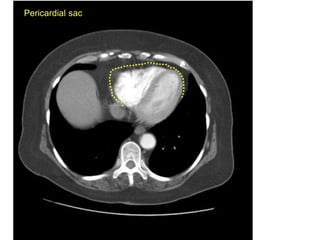

A

Pericardial sac